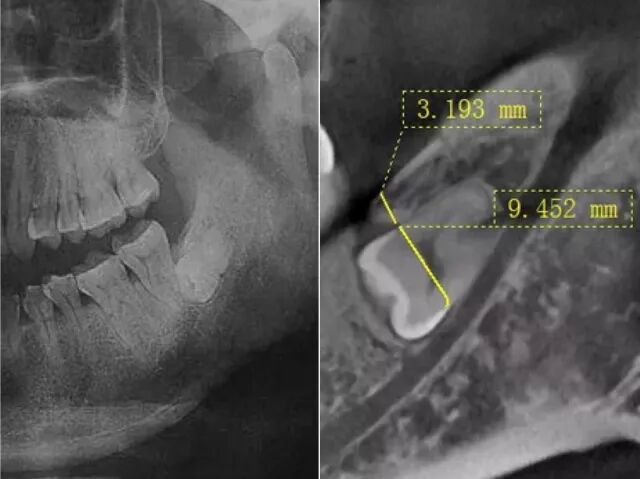

對於軟組織傷口的影響最小化(無損傷情況)。同時,不同類型和方向的刀頭更容易進入牙齒和骨骼之間的間隙,使牙易於拔除的同時,大大減低下頜神經管受損的風險。